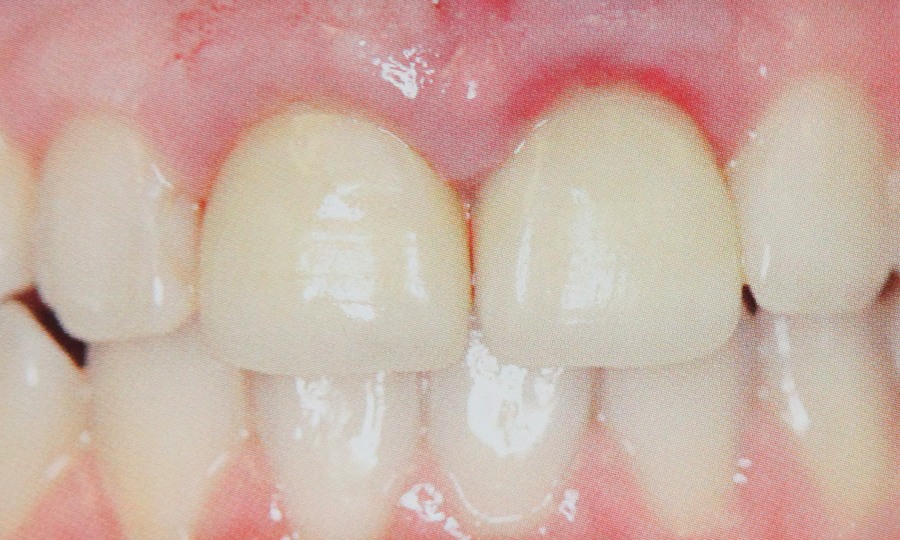

Tehnicile adezive directe de lucru cu materiale bazate pe rasini composite reprezinta o modalitate excelenta de restaurare estetica si minim invaziva a dintilor frontali. Obtinerea rezultatelor estetice asteptate este legata indesolubil de alegerea si utilizarea corecta, conform indicatiilor, a materialelor si tehnicilor de lucru adecvate, fiecarei situatii clinice.